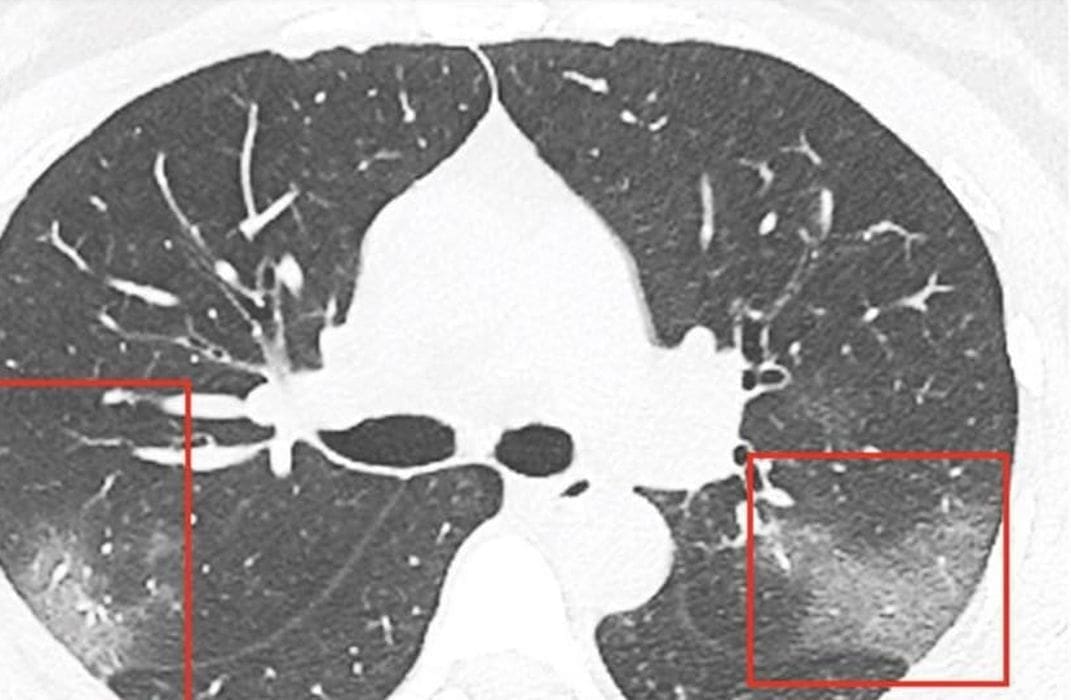

Liječnici pišu da se 33-godišnjakinja žalila na gubitak daha s obje strane pluća i ''pucketanjem'' koje je osjetila u njima. Na CT snimkama liječnici su uočili bijele sjene, poput takozvanog mliječnog stakla, što ih je upozorilo na to da su joj pluća djelomično ispunjena tekućinom. 33-godišnjakinji je nakon opsežnih pretraga i obavljenih testova dijagnosticirana zaraza koronavirusom.

Objavljene su fotografije njezina CT nalaza u trenutku primitka u bolnicu i tri dana kasnije, nakon što je počela primati terapiju.

Snimke pluća predstavljene su u znanstvenom časopisu Radiology, a članak potpisuje grupa liječnika istraživača Prve sveučilišne bolnice u Lanzhou - Junqiang Lei, Junfeng Li, Xun Li i Xiaolong Qi.